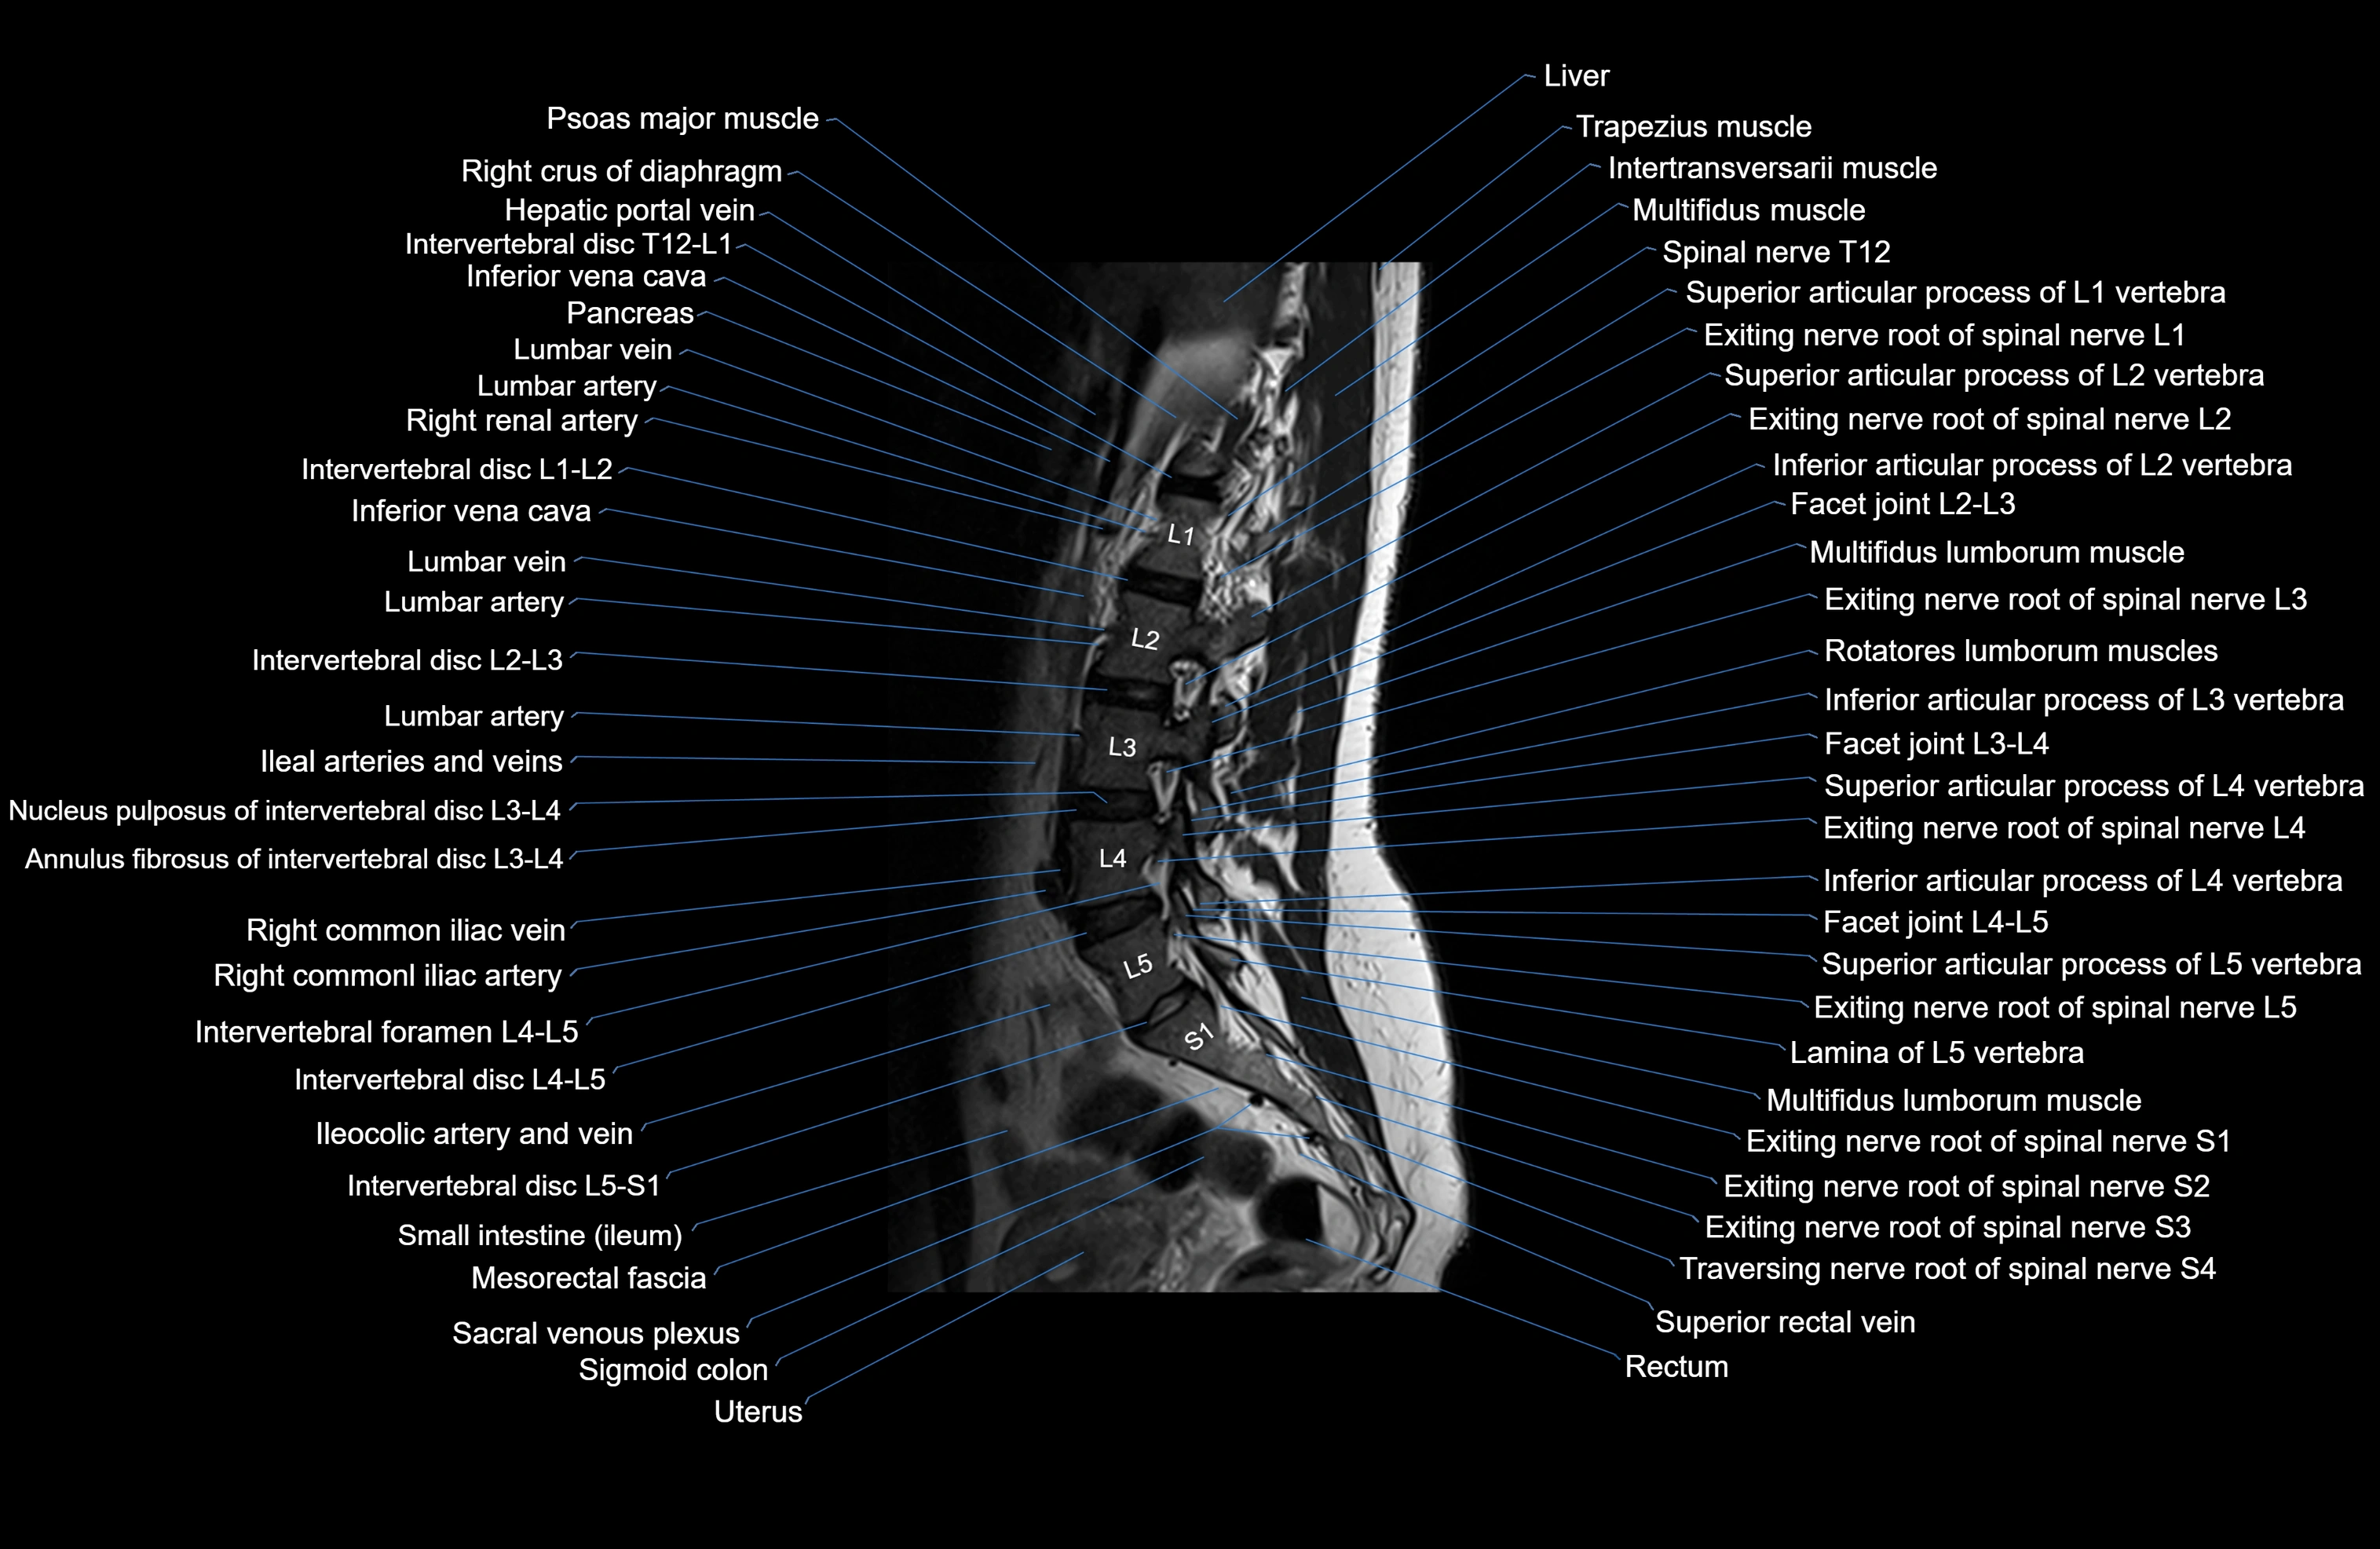

MRI images